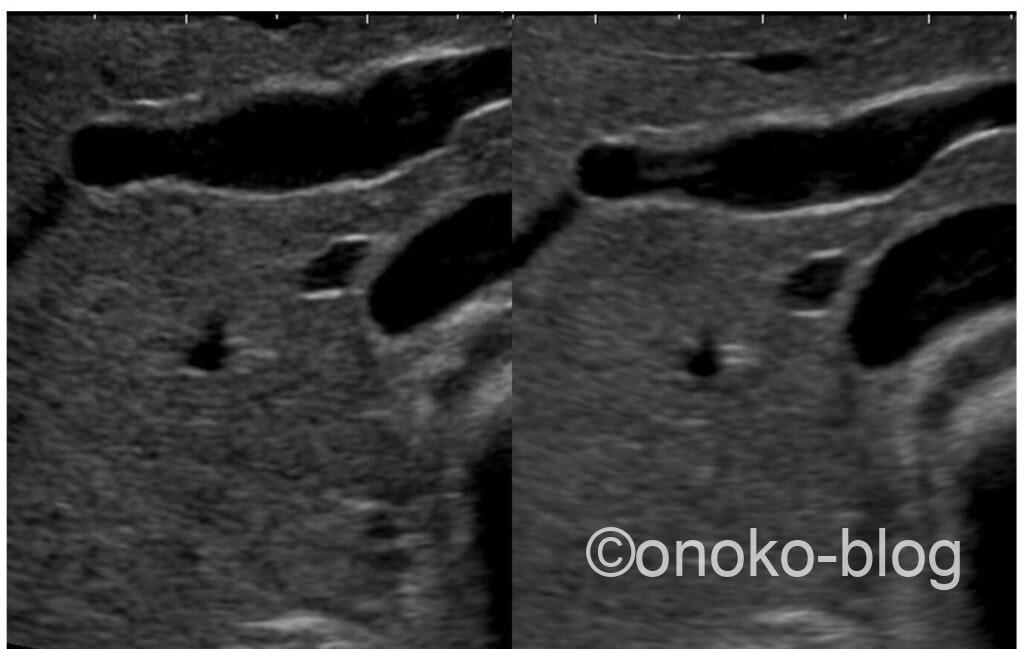

ふたつの画像を並べてみます。

左がWrite Zoom、右がRead Zoomです。こうやって比べてみると違いが分かりますね。

今のエコー機は解像度が素晴らしいのでRead Zoomでもじゅうぶんと思っていましたが、改めて比べると画像に違いがあるなあと私自身も気付くことが出来ました。